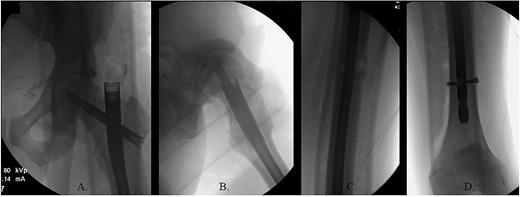

The patient was positioned supine on a fracture table. A guide wire was inserted through a 4-cm surgical incision proximal to the greater trochanter (GT) and was passed through a cannulated awl in a position slightly medial to the tip of the GT on the AP and center on the lateral (Fig. 2B). A (15-mm) entry reamer widened the opening (Fig. 2C). A rigid cannulated reduction rod and forceful malleting allowed the ball-tipped guidewire to cross the close reduced fracture, but too lateral and posterior distally (Fig. 3A and B). The cannulated flexible reamers encountered impassible blastic lesions within the proximal femur (Figs 3C and 5B).

(A) Ball-tipped guidewire slightly lateral position at the knee on the AP XR; (B) ball-tipped guidewire too posterior at the knee on the lateral XR; (C) flexible reamer within the proximal femur abutting blastic lesions.